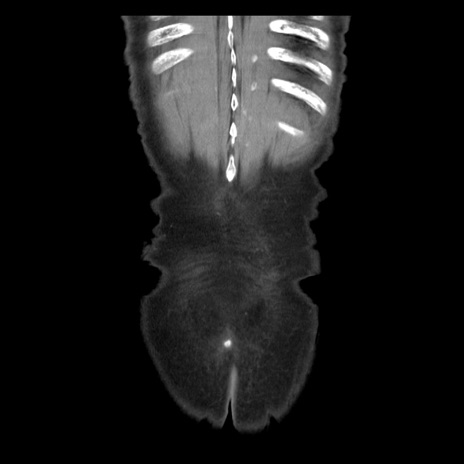

症例21(冠状断像)

【症例】70歳代男性

【現病歴】肝硬変・肝細胞癌にてかかりつけの方。約9時間前に食後より腹痛出現。症状が徐々に増悪し、嘔吐出現したため来院。

【既往歴】肝硬変、肝細胞癌(RFA、TACE後)